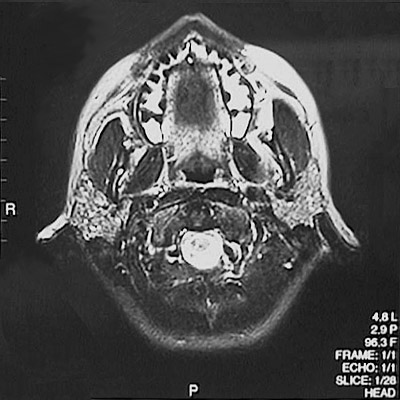

This is a normal axial T2 weighted MRI scan demonstrating the teeth in maxilla and tongue and pharynx and parotid gland and masseter muscle and medial pterygoid muscle and cervical spinal cord.